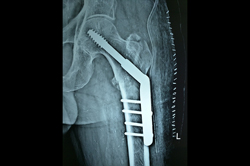

Periprosthetic Fracture THR